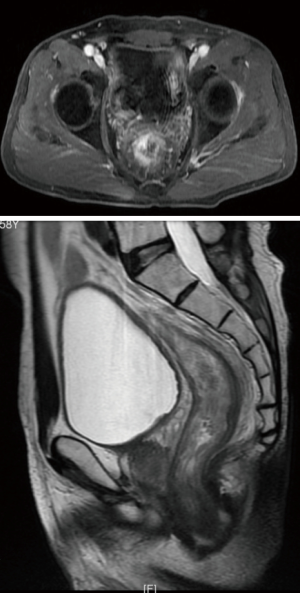

In the video, the patient is a 59-year-old man diagnosed to be moderately differentiated rectal cancer after CRT, and preoperative tumor staging was ycT3N1M0 by MR (Figure 2).